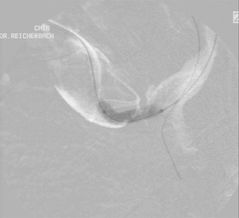

Die weiblich Brust hat die Eigenschaft, im Stehen der Schwerkraft zu folgen, und zwar umso mehr, je schwerer die Brust und je älter die Patientin. Der Port wandert dann mit der Brust nach unten und disloziert den Katheter aus der Vene. An den erweiterten Venen am linken Oberarm und Thorax erkennt man auch eine weitere Komplikation: die Thrombose der Vena subclavia.

Im Röntgen sieht man den dislozierten Katheter und die Kontrastmittelextravasation ins Mediastinum. Dorthin wurde auch das hochgradig gewebetoxische Adriamycin infundiert.